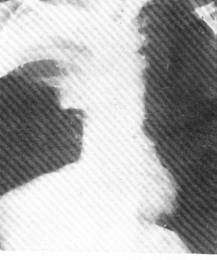

(一)中央型肺癌

多為一側肺門類圓形陰影,邊緣多多毛糙,有始有分葉表現;或為單側性不規則的肺門部腫塊,癌與專一性肺門或縱隔淋巴結融合而成的表現;也可以肺不張或阻塞性肺炎並存,形成所謂“S”型的典型肺癌的X線徵象。肺不張、阻塞性肺炎、預先性肺氣腫皆由於癌對氣管完全阻塞或部分阻塞引起的間接徵象。在體層攝片、支氣管造影可見到支氣管部分不規則增厚、狹窄、中斷或腔內腫物;視支氣管阻塞的不同程度可見有師尾狀、杯口狀況或者截平狀中斷。腫瘤發展至晚期侵犯鄰近器官和轉移淋巴結腫大,可見得有關肺門淋巴結腫大、縱隔塊狀影和氣管向健側移位;隆凸下淋巴結腫大可引起左右支氣管的壓跡、氣管分叉的高度變鈍和增寬以及食管中段局部受壓等;壓迫膈神經引起膈麻痹,可出現膈高位和矛盾運動;侵犯心包時,可引起心包積液等晚期徵象。